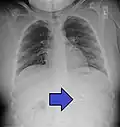

| An endoscopy image of the stomach, showing a foreign body in the form of a swallowed toothbrush. | |

One of the most common locations for a foreign body is the alimentary tract.

It is possible for foreign bodies to enter the tract from the mouth or rectum.